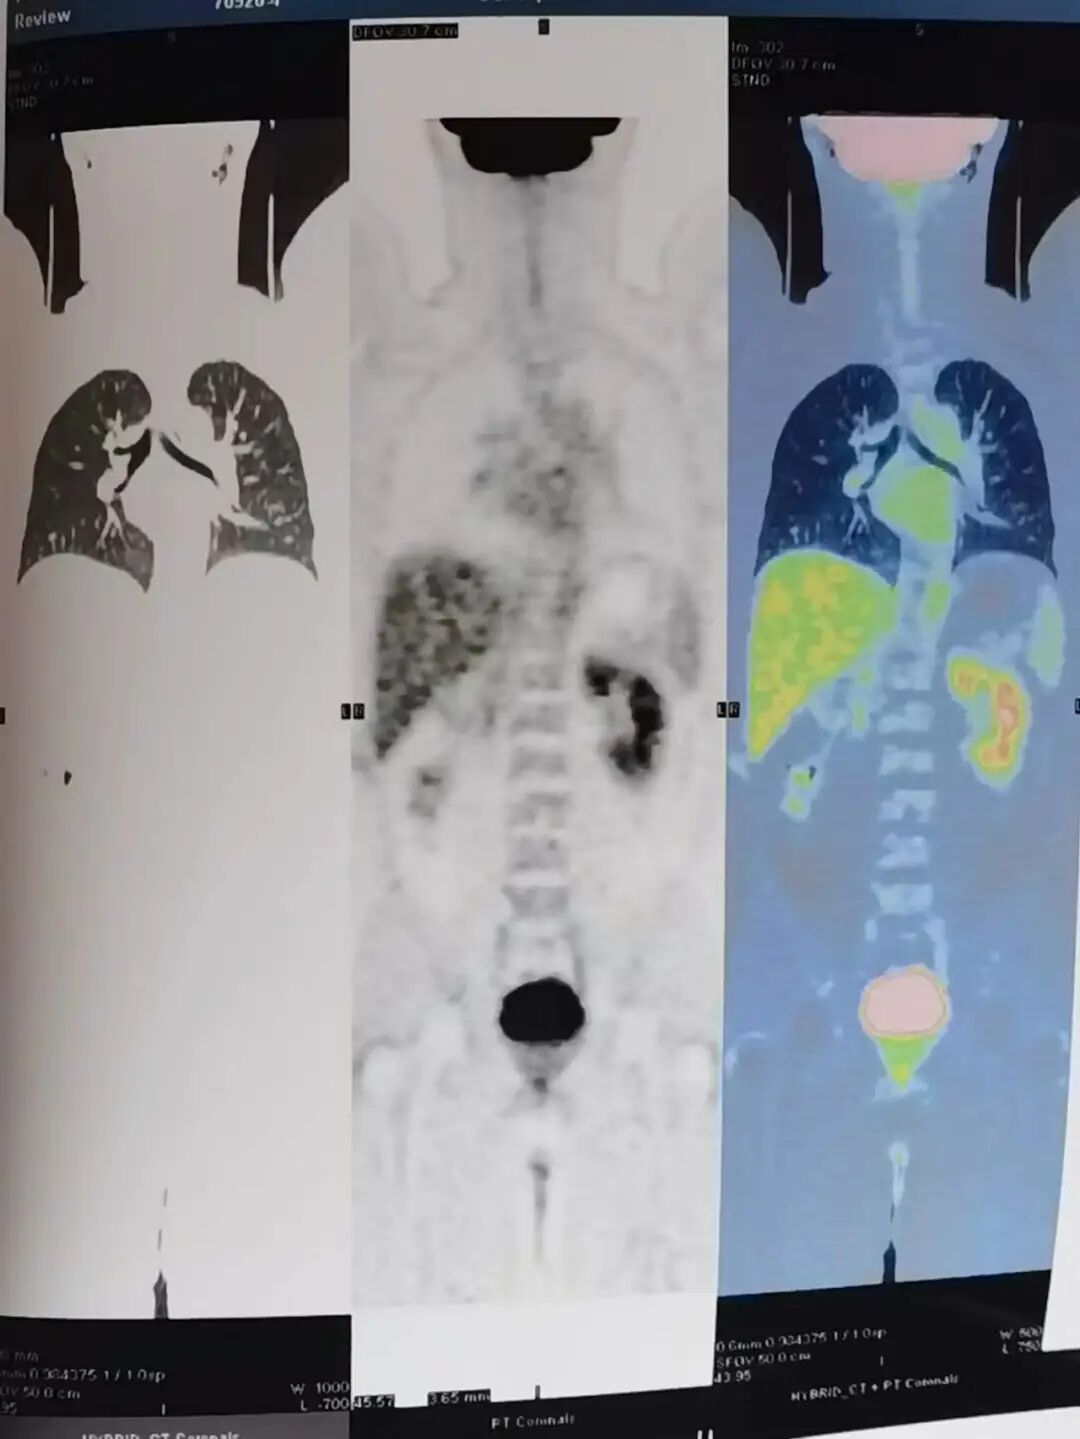

在坚持用药10个月后,我复查PET/CT后检查结果提示:骨骼上面的病灶已经基本失去活性。瘤块消失,骨痛缓解,医生告诉我,目前我的病情达到完全缓解,也就是医学上所称的“CR”状态。

2022年CR状态PET-CT检查结果

10个月后,我达到了完全缓解,并回到了工作岗位。